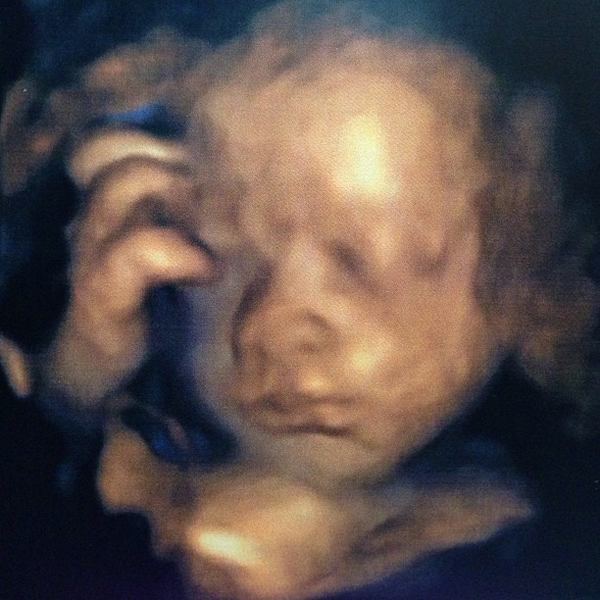

ชมกันชัด ๆ ภาพอัลตราซาวด์ หน้าลูกชาย ป๋อ ณัฐวุฒิ - เอ๋ พรทิพย์

ล่าสุด(28 มกราคม) ป๋อ - เอ๋ ก็ได้พากันไปอัลตราซาวด์ แบบ 4 มิติ หวังจะได้เห็นหน้าลูกชายแบบชัด ๆ ซึ่งก็ต้องลุ้นกันอยู่นานทีเดียว เพราะลูกชายของ ป๋อ ณัฐวุฒิ และ เอ๋ พรทิพย์ ไม่ยอมให้คุณพ่อคุณแม่เห็นหน้าง่าย ๆ เพราะเจ้าตัวคว่ำหน้าตลอด แต่ในที่สุด ลูกชายของ ป๋อ - เอ๋ ก็ยอมให้เห็นหน้าจนได้ แต่ก็ยังเอามือปิดหน้า แถมมีสายรกพาดหน้าอีก แต่แค่นี้ คุณพ่อป๋อ กับ คุณแม่เอ๋ ก็ชื่นใจสุด ๆ แล้วล่ะ